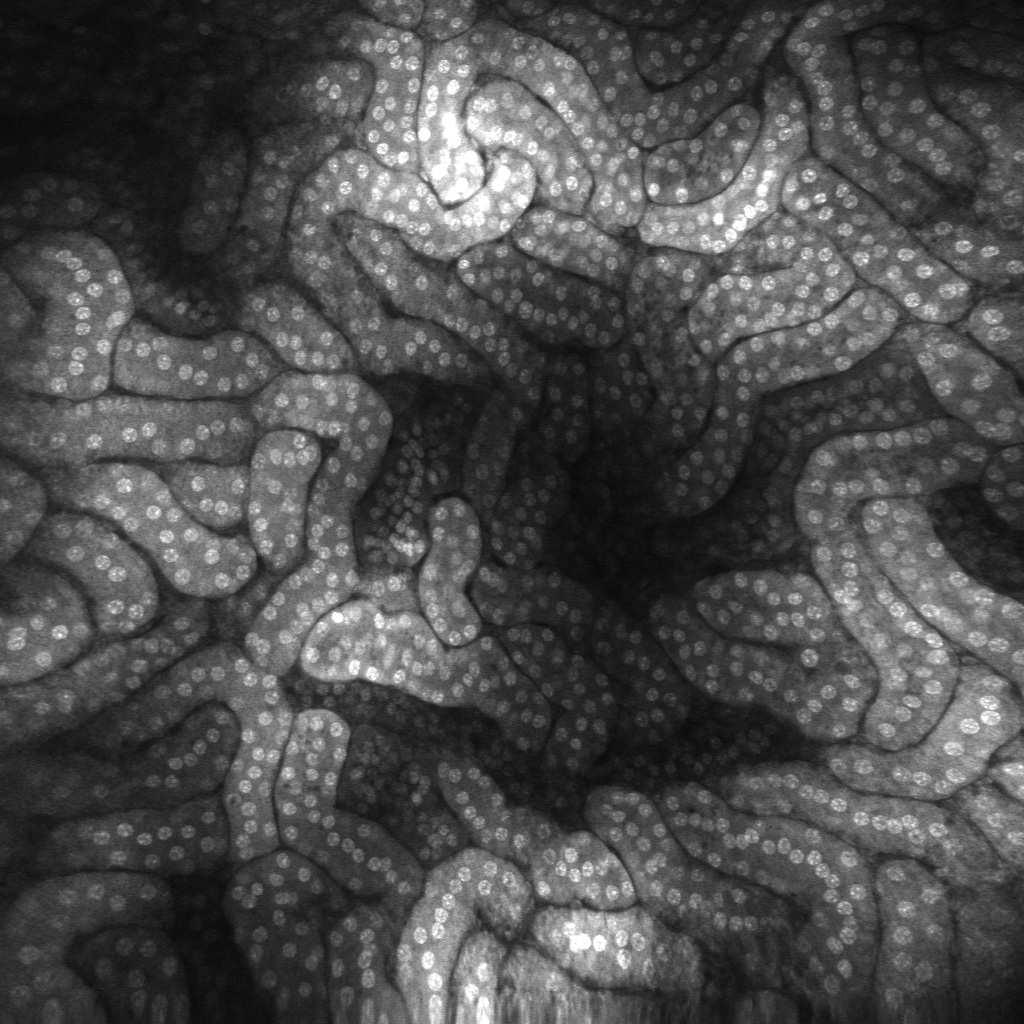

ViewnVivo® offers single-cell level live imaging, providing unique biological system insights and enabling users to see life connected. Developed with our patented confocal imaging technology, ViewnVivo® is a miniaturized in vivo imaging device that offers single-cell 3D live microscopic imaging in the palm of your hand.

Designed specifically for life sciences, pre-clinical and translational research, ViewnVivo® enables users to see systems biology in harmony, maintaining key cell structures, biological systems and cell-to-cell interactions to provide valuable translational results to accelerate drug discovery or unlock new study possibilities.

Superb resolution Using a distal end single scanning fibre rather than a proximally placed scanning fibre bundle provides unmatched lateral and axial resolution. The single fibre eliminates dead spaces and broken fibres, delivering high sensitivity and long lifespan. |